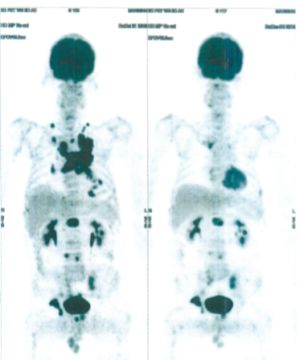

CASE NO: 3 (PROSTATE CANCER)

A middle-aged man with castration resistant prostate cancer, having failed all currently available cancer treatment, was very weak, and getting worse every day. The PET/CT scan showed he had massive bone metastases. After a few treatment, all the bone metastases went into remission. About 6 months later, he is still in remission.

CASE NO: 4 (PROSTATE CANCER)

A middle-aged man with castration resistant prostate cancer and massive bone metastases, failed all currently available cancer treatment, including with the new and expensive drug XTANDI. After a few treatment, most of the bone metastases went into remission, and the remaining ones are less active. Treatment will continue. Cases no: 3 and 4 show that terminal prostate cancer today can be cured with our new cancer treatment.